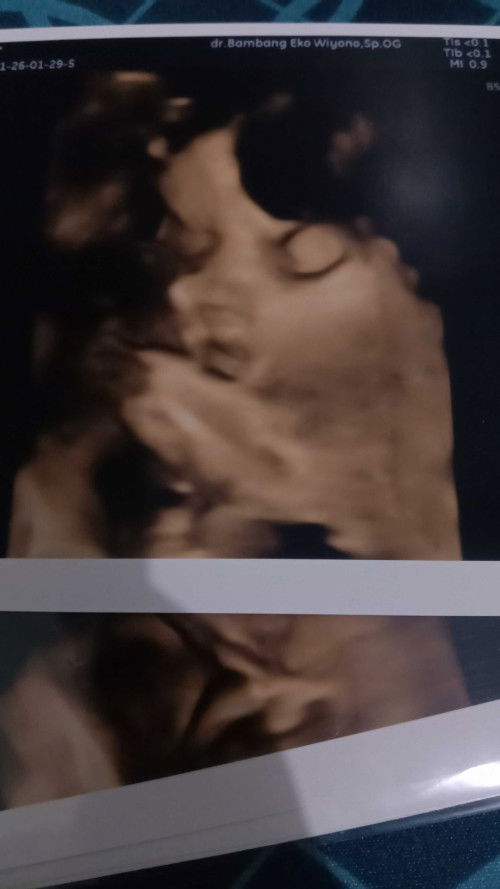

ini mnrt moms nrmal kan ya bibirnya kt dktrnya nrmal tp aku ovt stlh usg mnm vit ditm1 aja soalnya😢

anak ku kmrn di USG jga nampak ny gtu mba

keliatan Gemoy 😊 jadi mulut nya manyun

sama bun, ga pp insyaallah semua normal.

iya bun bener, kita sama. tapi aku mulai mempositif thinking kan pikiranku selagi dokter bilang engga pp🙏